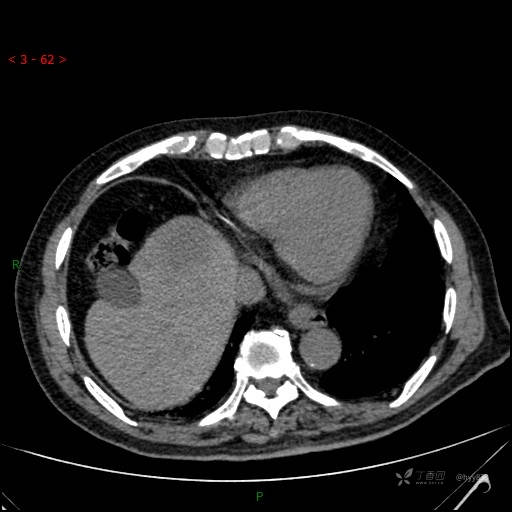

肝脏CT平扫

img